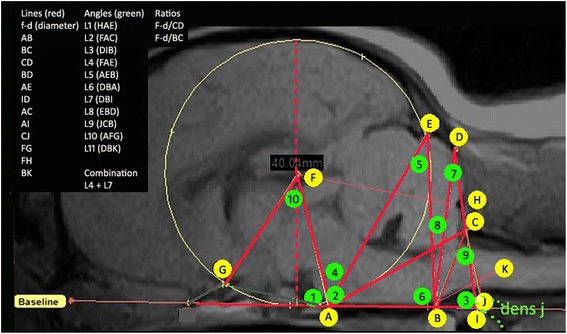

Next, using a DICOM reading software (Mimics® 14.12, Materialise, Belgium), a total of 11 structures were defined and 27 lines, angles and ratios were measured by SPK, initially blinded to SM status (Fig. 1, Additional file 1: Table S1). The mapping of the hindbrain and craniocervical junction was adapted from previous genetic and conformational studies undertaken in the Griffon Bruxellois [16, 17]. Dogs with narrow syringes or small central canal dilation are more likely to be asymptomatic at least with regard to the syrinx. The CKCS breed is very variable in size and head-shape. In view of this, two ratios were taken which reflected the size and shape of the caudal fossa and relating this to the height of the cranial fossa (f-diameter). The first ratio was the f-diameter (F-d) divided by the distance across the foramen magnum from the caudal point of the basioccipital to the rostral point of the atlas (line BC) and the second was F-d divided by the height of the supraoccipital bone (line CD) (Fig. 1). Since the MRI of the forebrain and olfactory bulb was not always available for analysis, in order to take account of the impact of brachycephaly and compensatory rearrangement of parenchyma and reduced caudal fossa, the two angles which most reflected these deviations in the hindbrain, angle 4 and angle 7 were combined (L4 + L7) (Fig. 2). The hypothesis being the smaller these two angles were, the greater the deviation and reduction in the neural parenchyma of the hindbrain and craniocervical junction.

Fig. 1.

Morphometric measurements of a Cavalier King Charles Spaniels whole brain. Measurements were chosen to best reflect the possible morphological changes observed in SM. All measurements start from one of these points: a dorsum of sphenoid-occipital synchondrosis, b basion of basioccipital bone, c rostral edge of the dorsal lamina of the atlas, d junction between supraoccipital bone and occipital crest, e most dorsal point of intersection of the cerebellum with the occipital lobe circle, f center of occipital lobe circle, g point at which the optic nerve deviates into the optic canal, h rostral edge of supra-occipital bone, i intersection point with the extended AB baseline caudally with extended line DC ventrally, j most rostral aspect of the dens of the axis bone and k extended line from point B along the best fit line of the ventral medulla oblongata to where it changes angle to the spinal cord